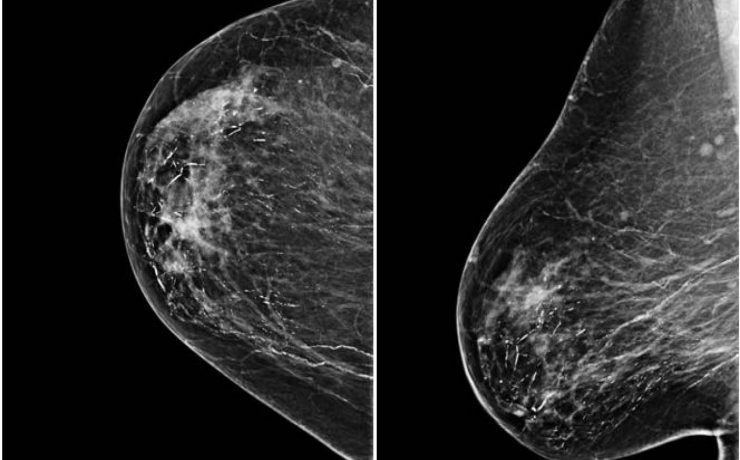

GINECOLOGÍA, TRES TRIMESTRES DEL EMBARAZO, MALFORMACIONES CONGÉNITAS Y OTRAS CONSIDERACIONES DEL EMBARAZO